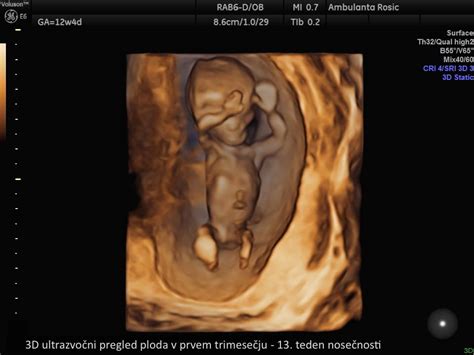

- 3D ultrazvok: Tridimenzionalna računalniška rekonstrukcija slike, ki omogoča boljši prikaz telesnih značilnosti.

3D/4D ultrazvoki so običajno samoplačniški in se priporočajo med 25. in 30. tednom nosečnosti za opazovanje plodovega vedenja.